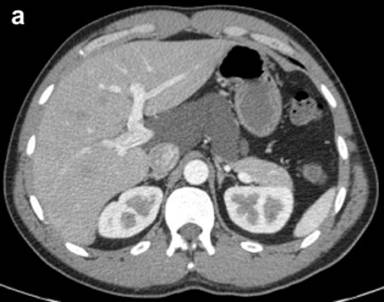

The patient was referred to our institution after a CT scan four months later showed the peripancreatic cyst stable in size measuring 9.0x4.5 cm (Figure 2a). Curved linear-array EUS showed a multiseptated cystic process near the head of the pancreas. The pancreas demonstrated some lobularity but did not meet EUS criteria for chronic pancreatitis (Figure 2b). The lesion was aspirated using the 19 gauge EUS-FNA needle and 5 mL of milky-white fluid was obtained. Laboratory analysis of the cystic fluid revealed a CEA of 2.0 ng/mL and an amylase of 276 U/L. Cytology was negative for malignancy, showed only benign appearing lymphocytes on the smear, and felt to be consistent with diagnosis of pancreatic cystic lymphangioma. Given the small amount of fluid aspirated, a triglyceride level was unable to be obtained due to partial solidification of material prior to analysis. No further diagnostic testing such as immunostaining was performed and patient was referred for surgical evaluation. Unfortunately, the patient failed to make this appointment and was lost to follow-up.

Figure 2. a. Contrast enhanced abdominal CT scan showing a cystic lesion adjacent to the body of the pancreas and extending into the porta hepatis from Case #2. b. Linear EUS image showing the anechoic cyst with several thin septae from the same patient. |